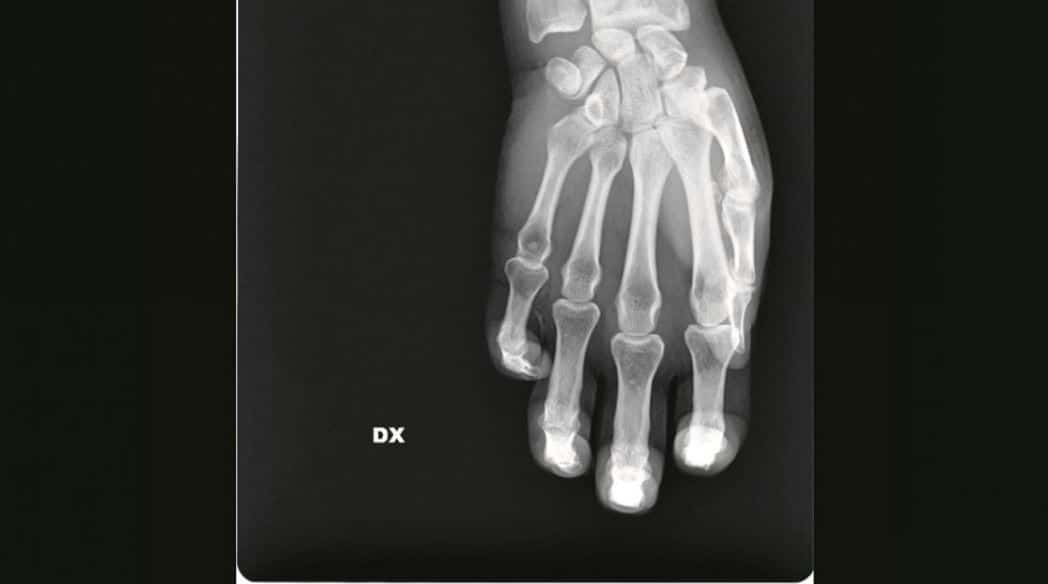

Una delle radiografie in mostra Credit: San Carlo di Milano

Da pugnali conficcati nell'addome a ossa rotte: la violenza sulle donne appare senza filtri nelle radiografie in mostra a Milano

La forza delle immagini contro la violenza sulle donne: una raccolta di foto e radiografie anonime raffigurano la parte più profonda delle vittime di violenza, quella che è stata ferita. Sono le immagini esposte nel rispetto dell’anonimato per scuotere le coscienze sul fenomeno in una mostra che verrà allestita nell’ospedale San Carlo di Milano, da giovedì 21 novembre a domenica 8 dicembre.

L’ideatrice della mostra di sensibilizzazione è la chirurga Maria Grazie Vantadori: “Le donne, spesso, non hanno la forza di raccontare. Ma i corpi e le lesioni parlano per loro, rivelano vertigini di orrore quotidiano. Per questo ho deciso di mostrare la violenza domestica come la vediamo noi al pronto soccorso: ossa rotte, nasi spaccati, occhi pesti, mani fratturate, polsi slogati, gambe rotte, coltellate, bruciature, morsi, segni di strangolamento, ferite da torture con pezzi di vetro. O addirittura un pugnale nella schiena. Lo scenario di una guerra nascosta nelle mura di casa che i numeri non riescono a raccontare”.